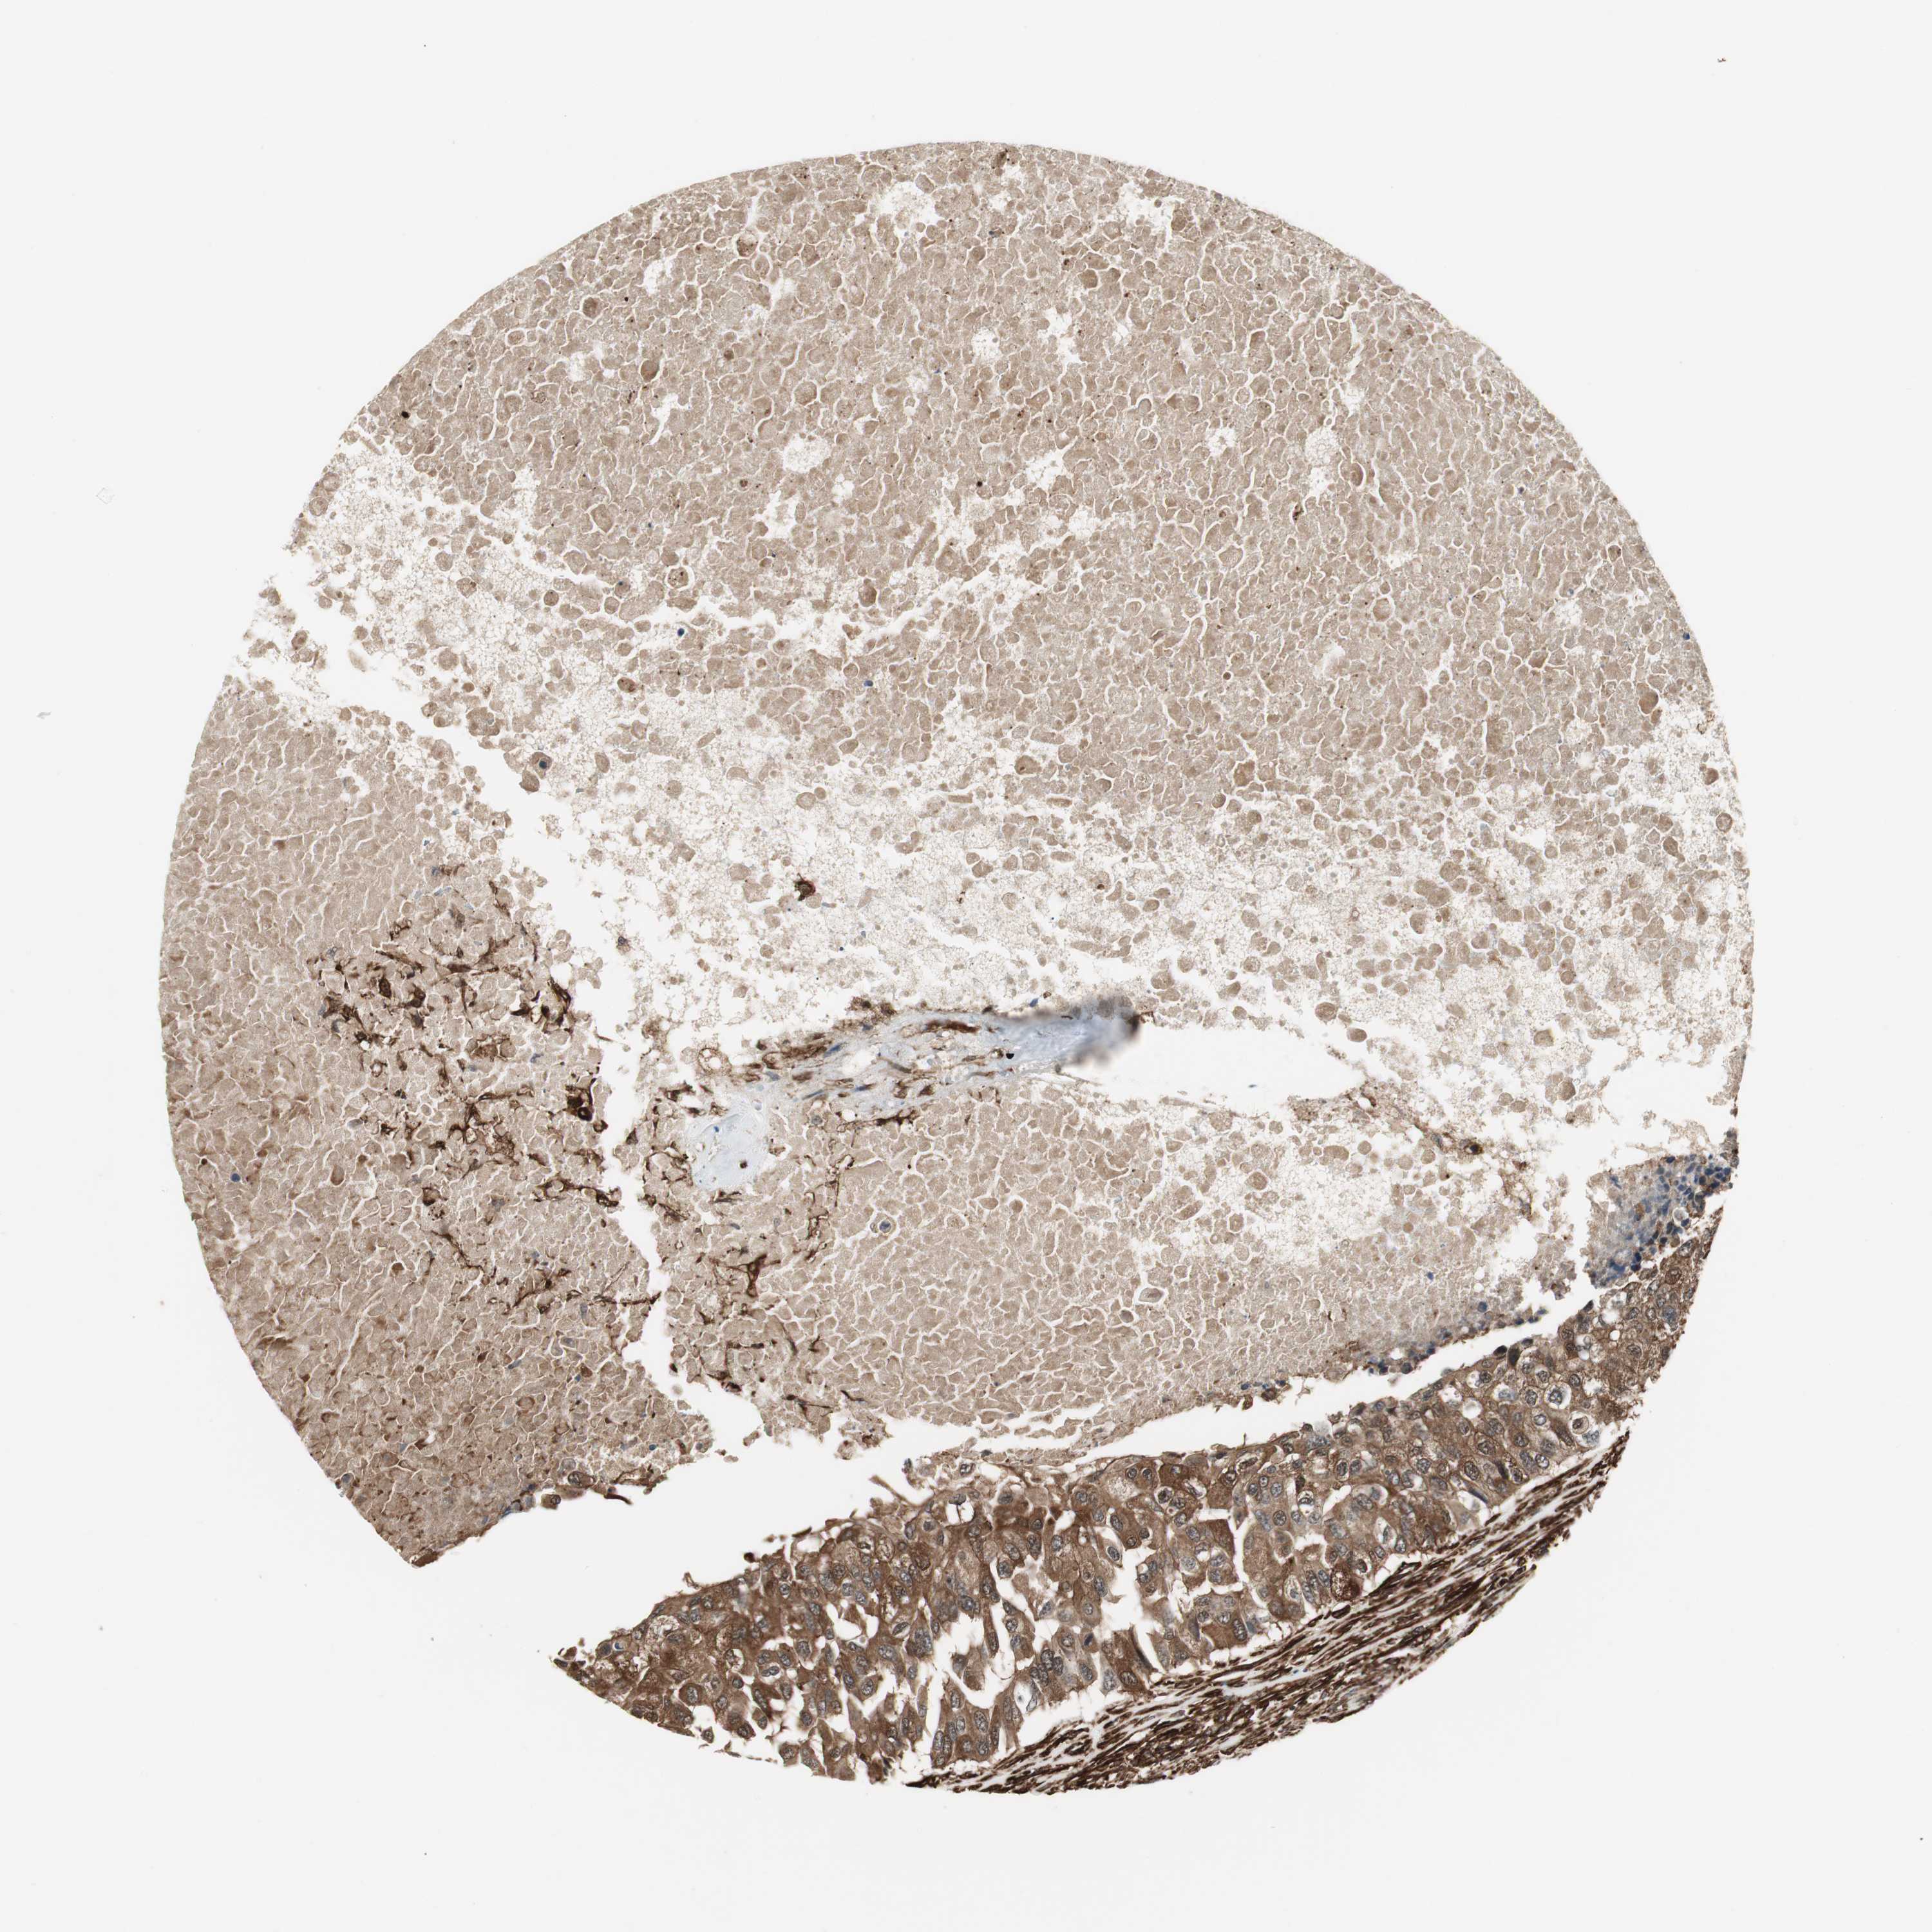

BRCA TCGA BRCA VALIDATION PROTEIN EXPRESSION